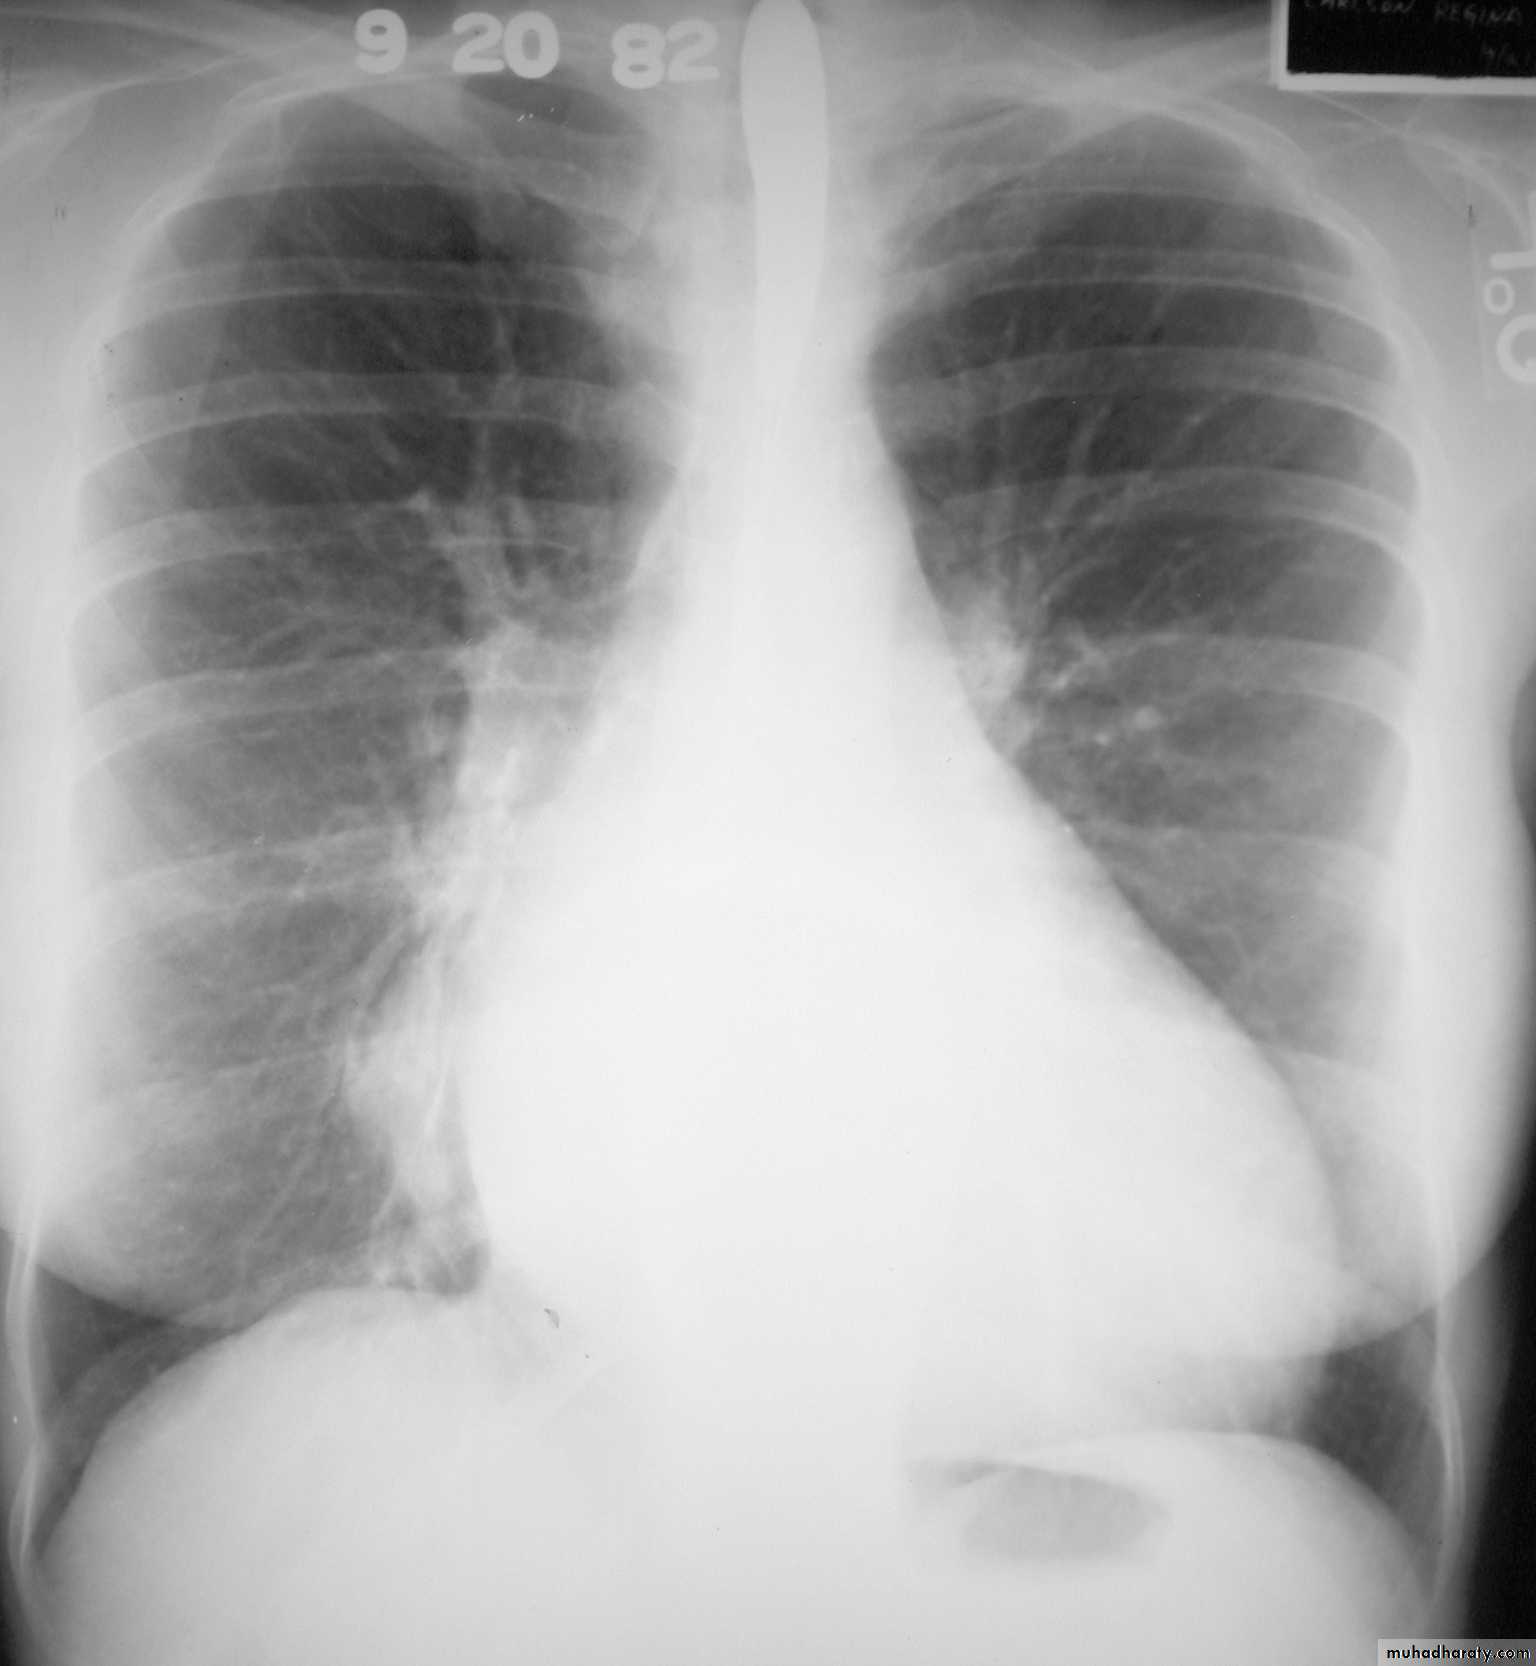

Hodgkin lymphoma of the middle mediastinum